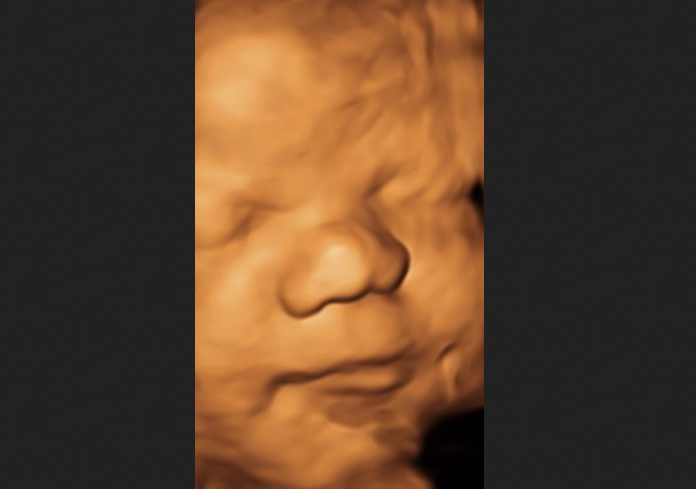

Mifepristone: Another Reason to Assert the Sanctity of Life May 9, 2026

Pro-Life Group to Supreme Court: Protect Moms and Babies From Abortion Pills May 8, 2026

113 Members of Congress Urge Supreme Court to Stop Mail-Order Abortions May 8, 2026

Woman Refuses Abortion, Rejects Pressure From Husband and Mother-in-Law May 8, 2026

As We Celebrate America’s 250th Anniversary, Remember Every Baby Has a Right to Life May 8, 2026

Rape Victim Traumatized Even Further When Seeing Dead Baby After Abortion May 8, 2026

WHO Will Push Every Country Worldwide to Legalize Abortion on Demand May 8, 2026